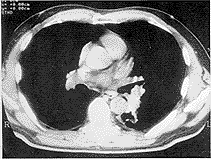

因刺激性干咳8a,加重2a,于1998年9月2日入院。查体:左下背部呼吸音较弱。CT示:左肺门软组织肿块,约2.1cm×4.0cm,密度不匀,CT值29.0Hu~48.0Hu,边缘不整,左下叶支气管腔变窄(图1、2),伴左下肺阻塞性炎症,纵隔淋巴结转移;支气管镜检示:左主支气管分叉处粘膜隆起呈肿块状,浸润生长堵塞背支开口。手术所见肿瘤位于下叶背段,约3cm×4cm×4cm,呈不规则形,肺门淋巴结肿大,融合成团。病理诊断:肺类癌,支气管断端处淋巴结可见转移癌,淋巴管内可见癌瘤。

左:纵隔窗右:肺窗

附图 胸部CT示

左肺门软组织肿块,大小约2.1cm×4.0cm,密度不均,CT值为29.0Hu~48.0Hu(左图),边缘不整,左下叶支气管腔变窄(右图)